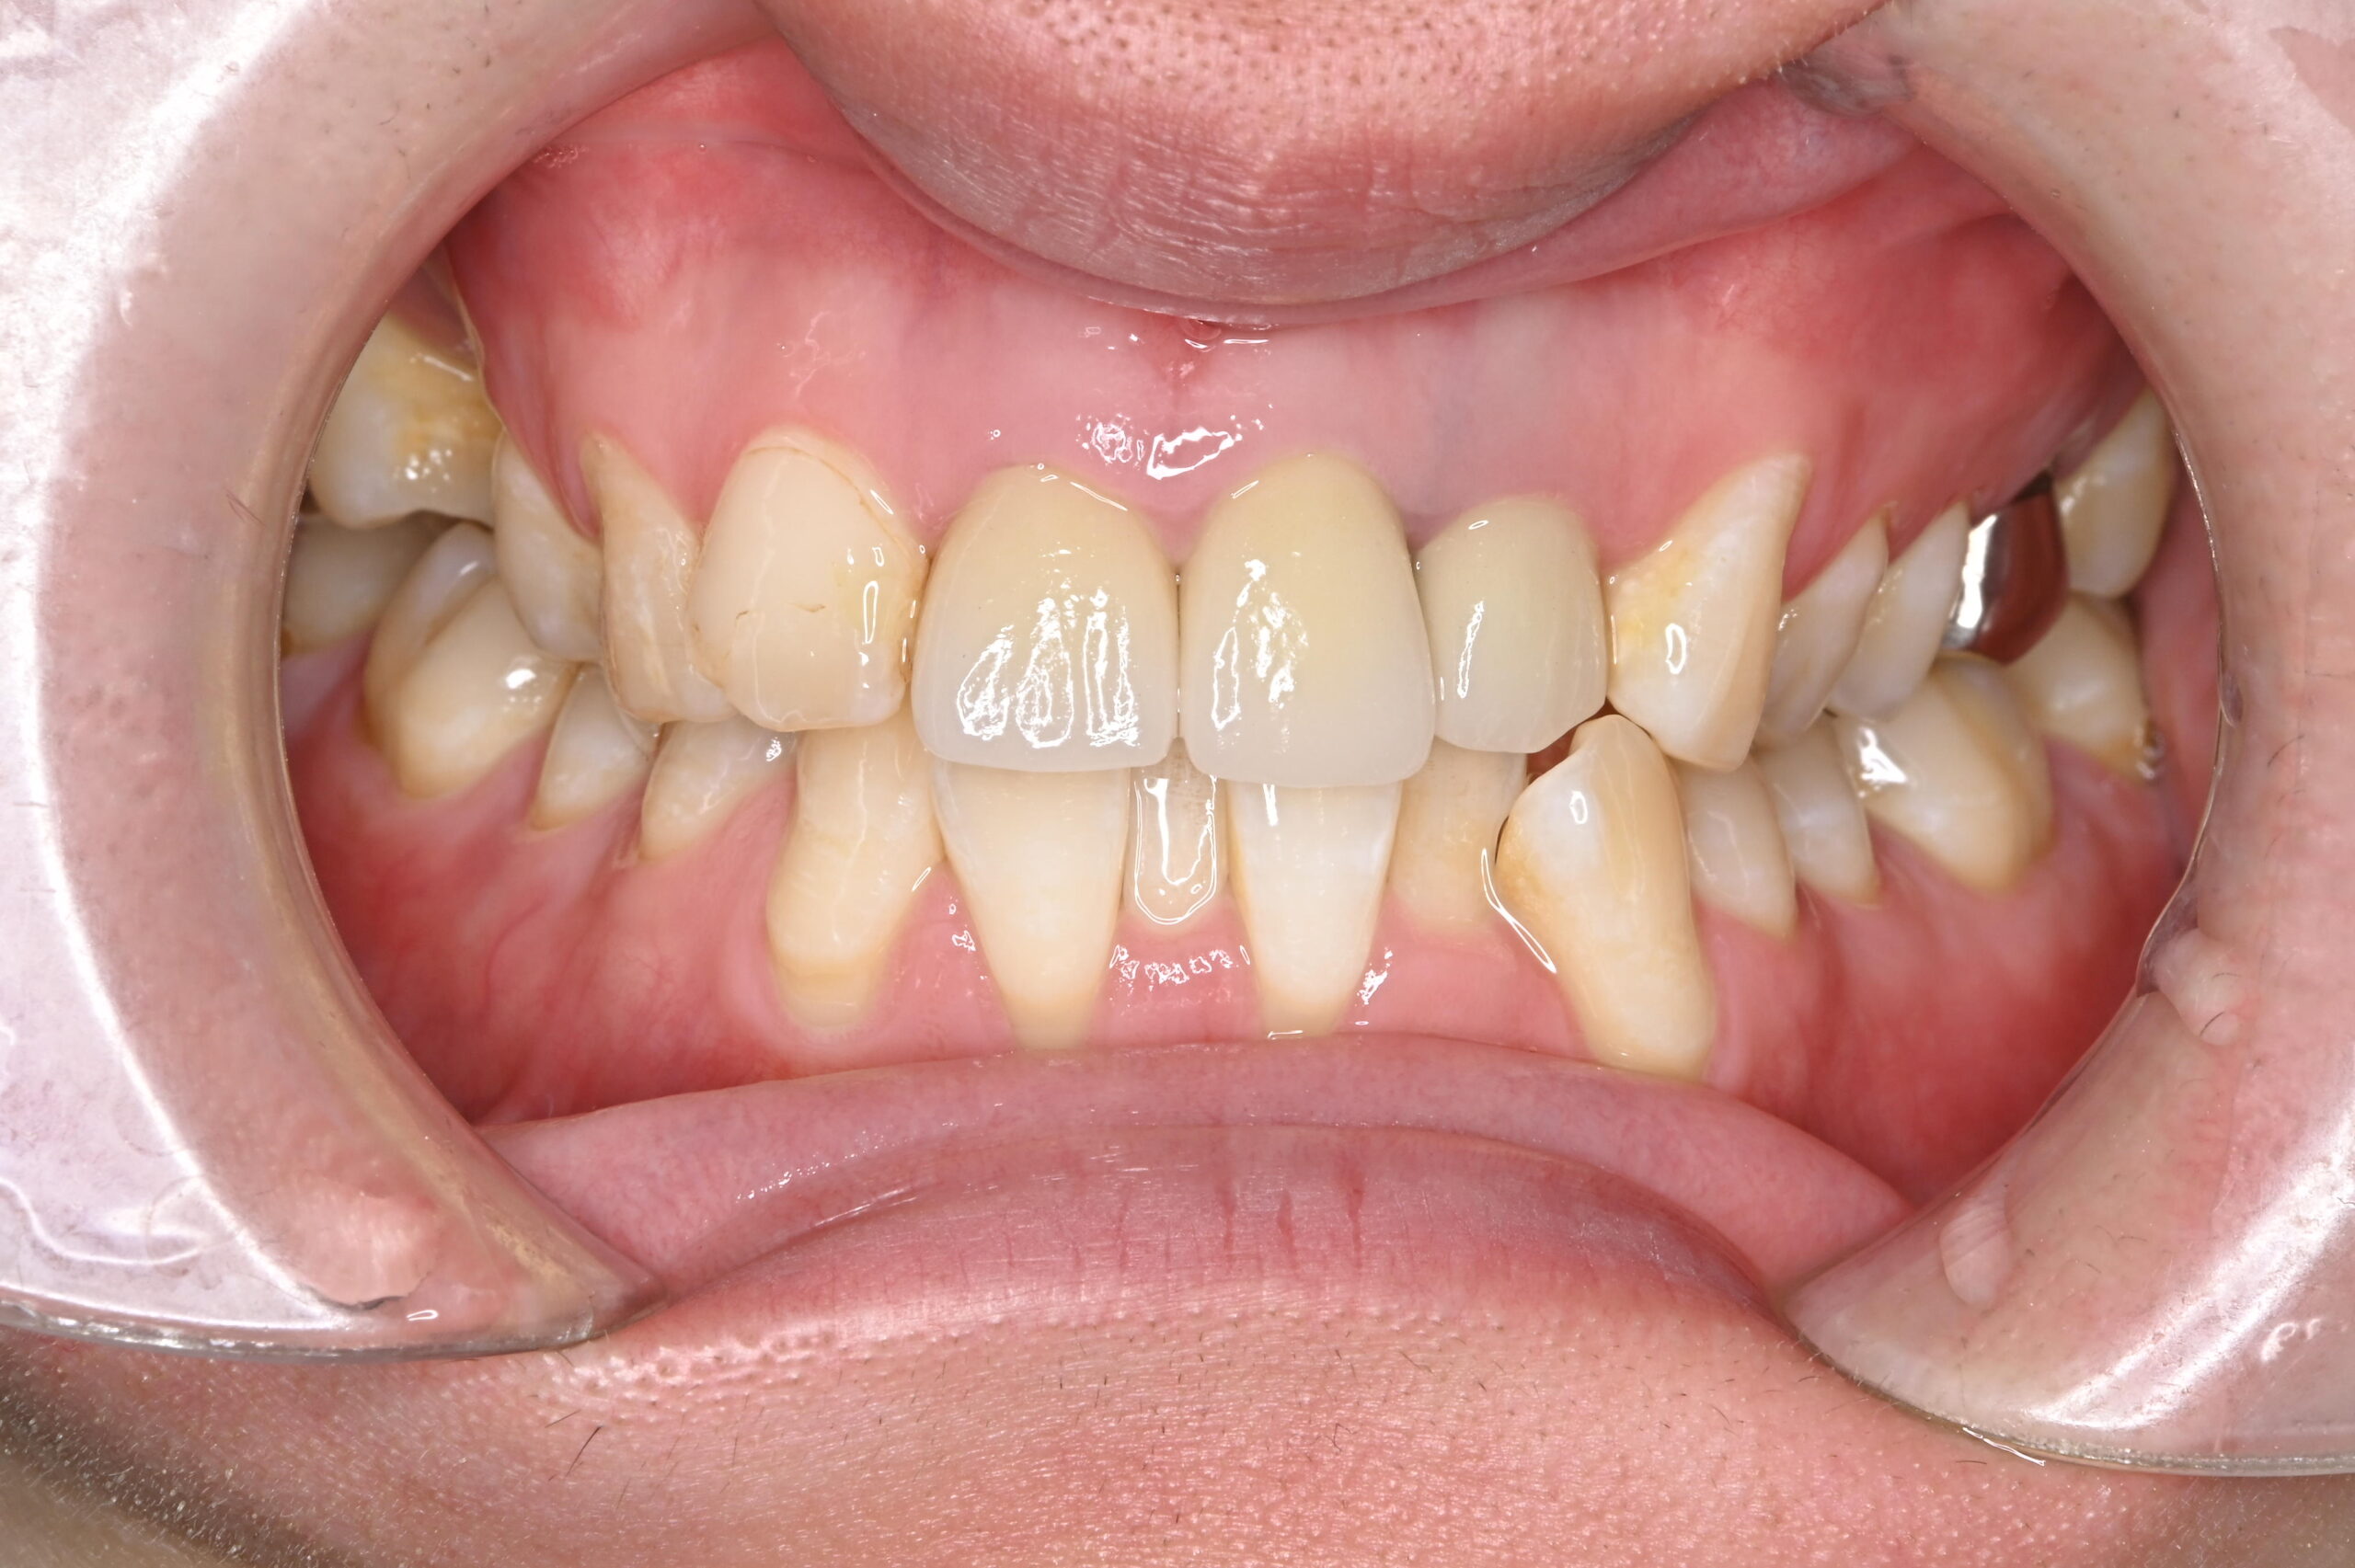

ジルコニアセラミックによる前歯3本の審美治療

年齢・性別

20代/男性

主訴

前装冠のブラックマージンが気になり、HPを見て「ぜひここでジルコニアセラミックにしたい」と来院

治療方法

ジルコニアセラミック(左上1,右上1・2 )

費用

ジルコニアセラミック 110,000円×3本

合計 :330,000円

*価格は税込です

メリット

• ブラックマージンの心配がない

• 自然なツヤと色合いがずっと保たれる

デメリット・

副作用

• 特にセラミック部分に欠ける可能性がある

• 高価である